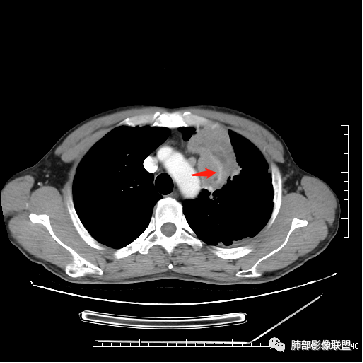

男,47岁,咳嗽咳痰一月。病灶位于左内乳动脉内缘,定位肺内,呈团片状异常密度影,整体沿支气管气管束走形分布,由肺门达胸膜下,于近肺门侧病灶形态相对较小,病灶远端相对较大,病灶整体密度偏均匀,强化偏明显,病灶内见多发支气管扩张并粘液栓形成,且扩张支气管粗细不均,直达病灶以远,病灶内血管走形正常、粗细均匀,病灶周围见边缘模糊磨玻璃及少许腺泡结节。左肺门及纵隔略大淋巴结,左侧胸膜局限性增厚。诊断:左肺上叶前段异常密度影,炎性肉芽肿性病变可能,结核不能除外,建议穿刺活检除外恶性肿瘤。

4.病灶整体轻中度强化,强化较均匀,局部见多个管状低密度影,边界清,考虑支气管粘液栓;病灶局部可小灶样的低密度区,未见强化,考虑坏死灶,坏死灶周围见明显强化的壁,壁清楚、光整,未见中断,倾向炎性肉芽肿的坏死;

5.病灶内血管部分走形自然,部分走形僵直、粗细不均,提示病灶有部分破坏力,但是不强;

6.病灶与纵隔胸膜呈“糊墙”样改变,倾向炎性病灶;

2.双上肺多发病灶,左肺上叶病灶沿血管支气管束分布,由外朝内,以平直收缩为主,周围有斑片渗出,胸膜糊墙,支持炎性病灶或是伴有肿瘤灶可能性。

3.病灶内多支支气管粘液栓,炎性及恶性均可,但是炎性多于恶性;强化杂乱不均,病灶内小灶坏死比规则,支持炎性肉芽肿病变。

5.  本例的焦点主要集中在结核与周围型肺鳞癌的鉴别诊断上!

病灶与大气道的关系未能满意呈现,但如此大范围病灶紧贴胸膜却未见胸壁纵隔组织结构侵犯破坏是不大符合肺鳞癌的生物学行为的。